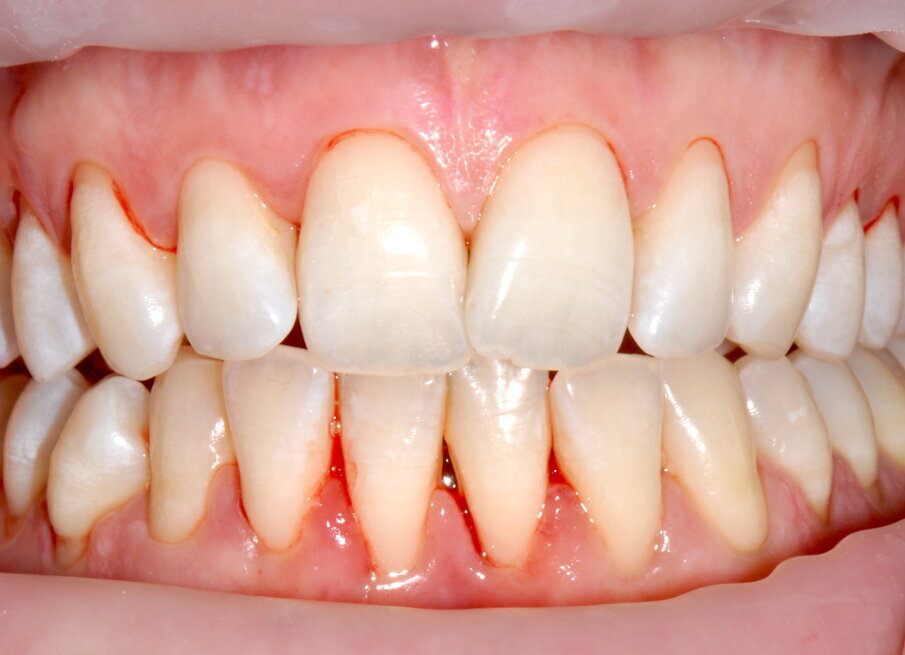

- Applicazione del rilevatore di placca bifasico: permette la distinzione fra i depositi di placca recenti da quelli meno recenti ( 1a-1c);

Figg. 1a-1c - Applicazione del rilevatore di placca che verrà usato come guida durante la terapia, nel versante vestibolare (1a), palatale (1b) e linguale (1c). Si noti lo scarso livello di igiene orale domiciliare e l’assenza di utilizzo dei presidi interdentali.